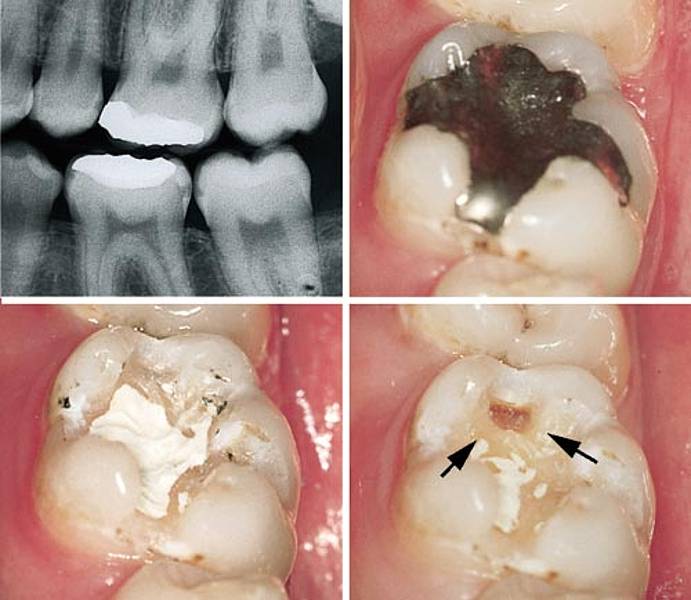

Vococid Vococid wird für die SäureÄtzTechnik verwendet und enthält 35% Orthophosphorsäure Die blaue Einfärbung des Gels bzw der Flüssigkeit ermöglicht eine sichere Applikationskontrolle Vococid kann zur Schmelzätz oder TotalEtchTechnik verwendet werden und ist wahlweise als Gel oder Flüssigkeit erhältlich Produktdetails Vococid. In einem zweiten Schritt wird bei dem als SäureÄtzTechnik bezeichneten Verfahren die aufgeraute Oberfläche des Zahns mit einem Monomerengemisch versetzt Die Monomeren gelangen in die Hohlräume und polymerisieren dort aus Dadurch kommt es zur engen Verbindung von Zahnschmelz und Polymerisat. SäureÄtzTechnik Die SäureÄtzTechnik ist eine Füllungstechnik, bei der vor dem Einbringen des plastischen Füllungsmaterials in die Kavität die Zahnhartsubstanz mit Hilfe von Säuren angeätzt wird.

Auch Klebetechnik oder SäureÄtzTechnik (SÄT) genannt, ist eine Methode zur Befestigung von Zahnersatz in der Zahnmedizin Die Adhäsivtechnik wird sowohl bei KompositFüllungen und beim Zementieren von Keramikfüllungen als auch beim Befestigen von Kronen, Verblendschalen (Veneer) und Klebebrücken mittels Komposit sowie bei der. Ätzen von Schmelz und Dentin im Rahmen der SäureÄtzTechnik Enthält 34 %ige Phosphorsäure In kräftiger ab 34,19 € Lieferbar iBOND® Etch Gel Ätzen von Schmelz und Dentin für die ÄtzBondTechnik Vorteile Enthält ab 11,59 € Eingeschränkt lieferbar. Das Verfahren selbst wird SäureÄtzTechnik (SÄT) genannt Durch die Mikroretention wird die Dichtigkeit einer Füllung erheblich erhöht Sie führte erst zum vertretbaren Einsatz von Kunststoffen in der restaurativen Zahnmedizin Systematik Die Mikroretention wird folgendermaßen erreicht.

Die Adhäsivtechnik (Lat adhaerere ‚anhaften‘) ist eine Methode in der Zahnmedizin zur Befestigung von Zahnrestaurationen mittels Kunststoff Sie wird sowohl bei KompositFüllungen und beim Zementieren von Keramikfüllungen als auch beim Befestigen von Kronen, Veneers (Verblendschalen) und Klebebrücken mittels Komposit sowie bei der Fissurenversiegelung angewandt.